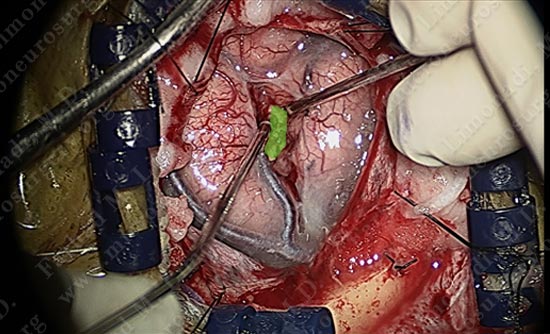

Micro-instruments are utilized in opening the interval between the two gyri underneath which the tumor is hidden. Patient is being examined in short intervals.

The superficial pole of the tumor is outlined in green.